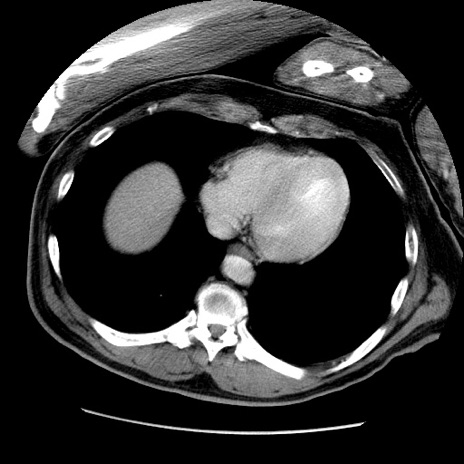

症例22(横断像)

【症例】50歳代男性

【主訴】腹痛

【現病歴】AVMからの被殻出血のため回復期リハ病棟入院中。 本日午後3時頃急に下腹部痛が出現した。

【既往歴】AVM、被殻出血、虫垂炎、高血圧

【身体所見】意識晴明、左半身不全麻痺、会話の理解は良好、36.5°C、腹部:膨隆、全体に板状硬、下腹部正中に圧痛点あり、反跳痛-、筋性防御不明、右下腹部にope scar

【データ】WBC 9400、CRP 0.06